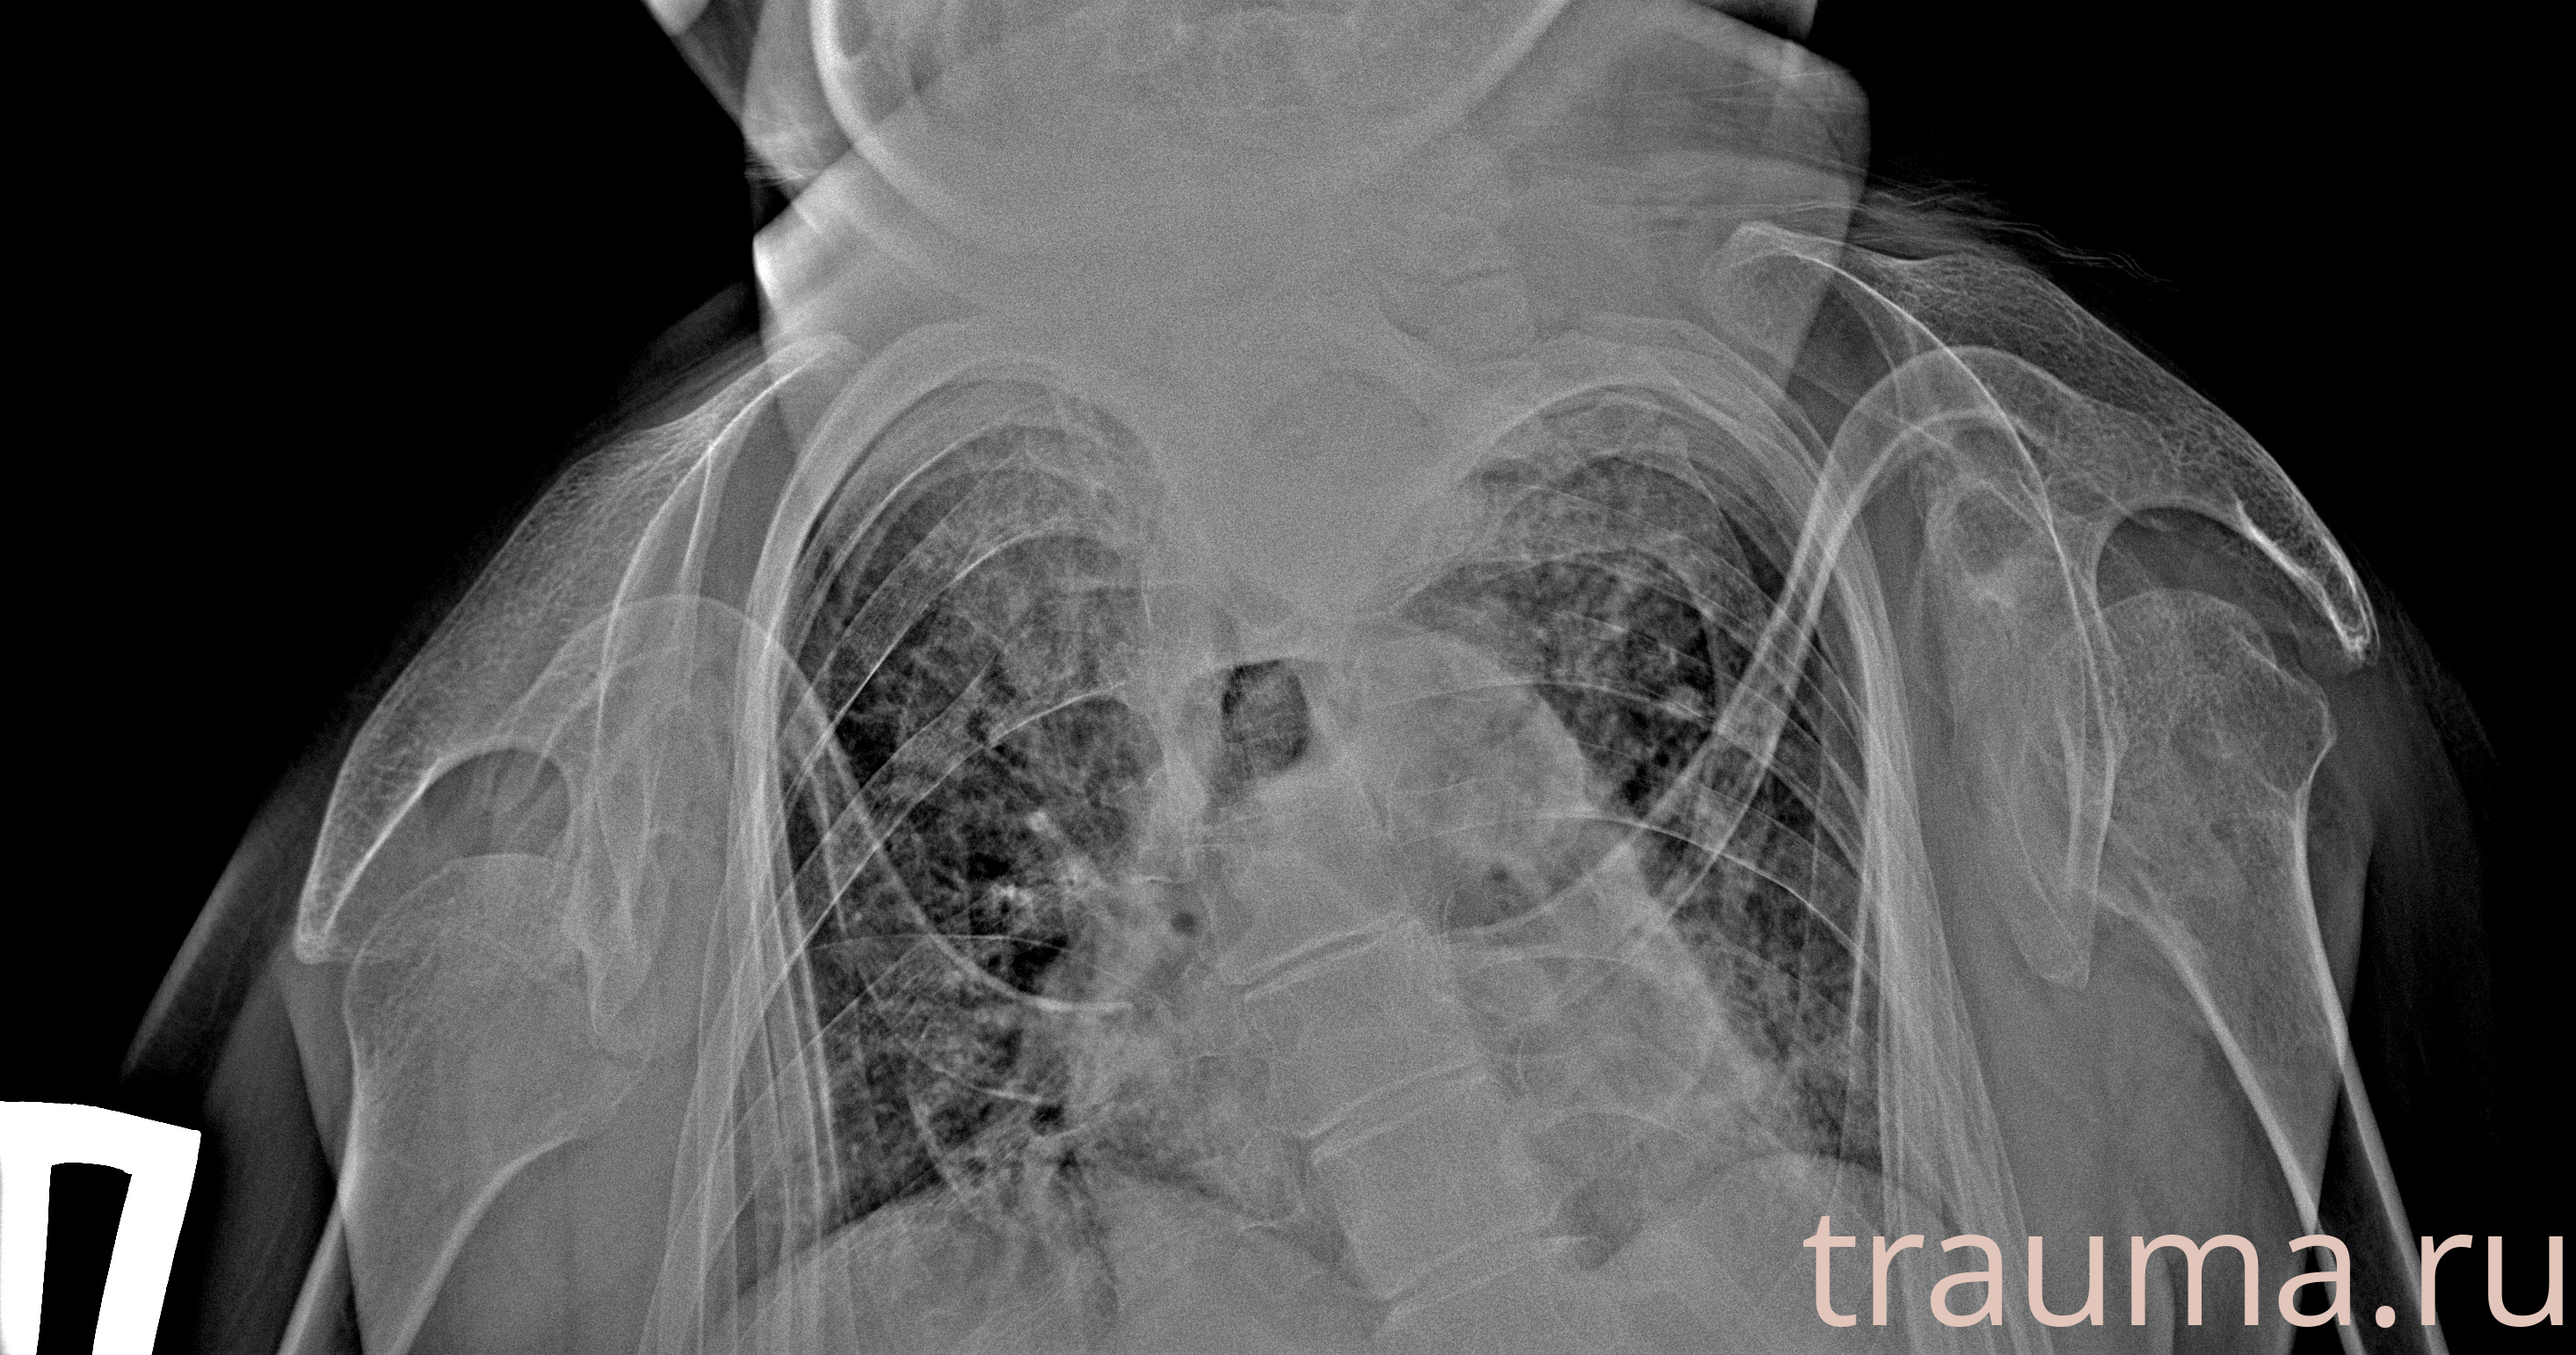

Рентген на дому: по вашему адресу приезжает врач-рентгенолог, травматолог-ортопед с мобильным рентгеновским аппаратом, проводит диагностику травмы или заболевания, делает необходимые рентгенограммы, дает рекомендации по дальнейшему лечению. Получить качественные снимки в домашних условиях возможно благодаря уникальной методике, разработанной МосРентген Центром для института  Склифосовского